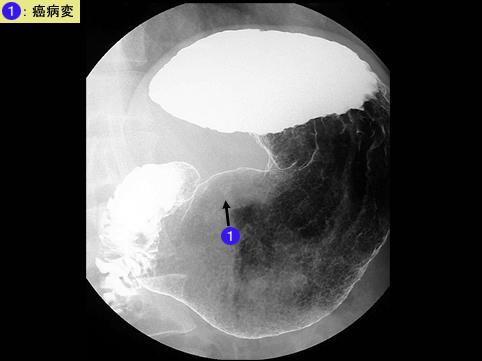

疾病(病理主体)的分类恶性上皮性肿瘤/印戒细胞癌

部位(按器官分)胃(部位)/胃角

检查方法X线

肿瘤的肉眼分类0型(表在型)/III型(III+IIc)

肿瘤最大直径10~14

肿瘤的深度sm